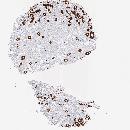

CANCER BREAST CANCER Show tissue menu

BRCA TCGA BRCA VALIDATION PROTEIN EXPRESSION

ANTIBODIES

AND

VALIDATION